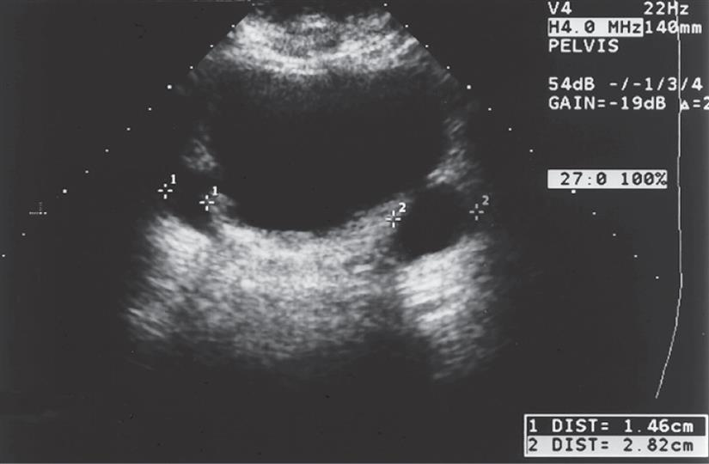

Fluid in Morison’s pouch is seen anterior to the right kidney in this sagittal view. Arrows, Fluid; L, liver; RK, right kidney. **Ascites**